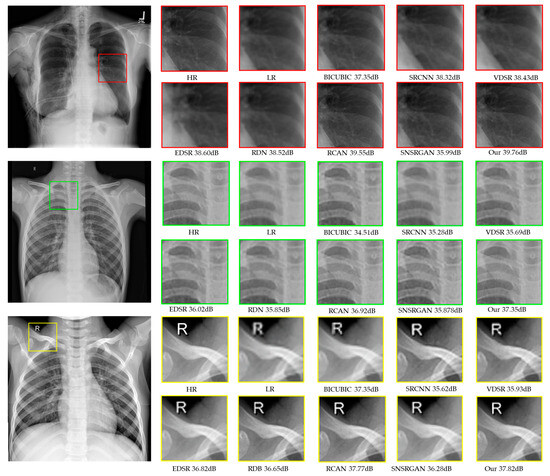

| X4 | BICUBIC [24] | 37.35 dB/0.907/0.940 | 34.51 dB/0.901/0.910 | 33.35 dB/0.907/0.910 |

| SRCNN [18] | 38.32 dB/0.9392/0.941 | 35.28 dB/0.921/0.929 | 35.62 dB/0.912/0.932 | |

| VDSR [14] | 38.42 dB/0.938/0.940 | 35.69 dB/0.917/0.936 | 35.93 dB/0.92/0.938 | |

| EDSR [16] | 38.60 dB/0.944/0.967 | 36.02 dB/0.925/0.945 | 36.82 dB/0.932/0.959 | |

| RDN [17] | 38.52 dB/0.939/0.972 | 35.85 dB/0.912/0.968 | 36.22 dB/0.925/0.958 | |

| RCAN [8] | 39.55 dB/0.947/0.982 | 36.92 dB/0.927/0.972 | 37.77 dB/0.921/0.953 | |

| PROPOSED | 39.76 dB/0.944/0.991 | 37.38 dB/0.932/0.989 | 37.82 dB/0.937/0.982 | |

| RCAN [8] | 39.55 dB/0.947/0.982 | 36.92 dB/0.927/0.960 | 37.77 dB/0.931/0.953 |

| SNSRGAN [5] | 35.99 dB/0.924/0.983 | 35.87 dB/0.910/0.979 | 36.28 dB/0.915/0.943 |

| PROPOSED | 39.76 dB/0.944/0.991 | 37.38 dB/0.932/0.989 | 37.82 dB/0.937/0.982 |